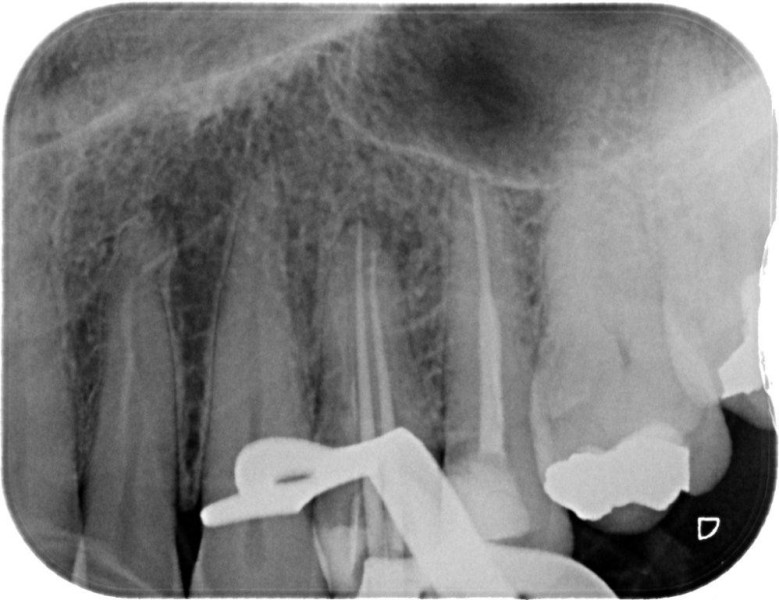

Molar retreatment

Re-treatments are more difficult than primary root canal work as the filling material has to be removed and any errors in the previous treatment corrected where possible.